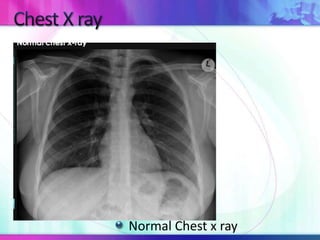

Normal Chest x ray